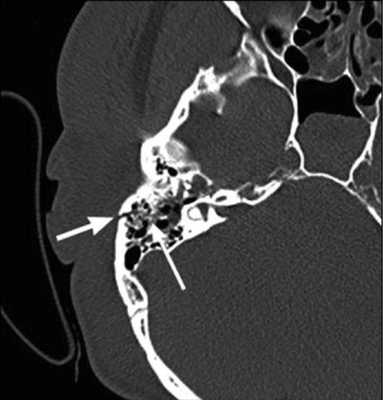

Компьютерная томография является оптимальным вариантом для исследования костей, в том числе черепа. Костная ткань хорошо поглощает рентгеновские лучи, в результате получают четкие ее изображения. Данный метод незаменим в диагностике скрытых переломов и трещин, он хорошо выявляет деструктивные изменения.

На КТ-снимке виден перелом пирамиды височной кости (указан стрелками)